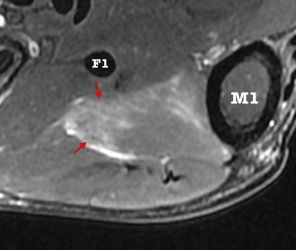

Oedème post-traumatique au niveau de l'Opposant du I

Triangulaire, recouvre M1

Sur toute la hauteur du versant externe de la face antérieure de M1